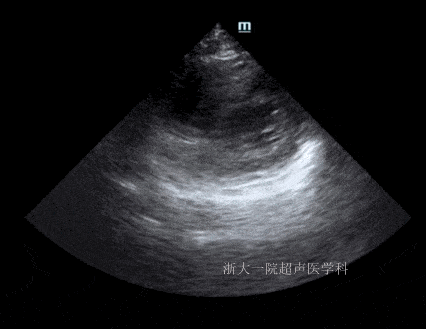

入院48h超声:左室壁未见节段性运动异常.超声提示图3:ef:51%.

图室,意外的发现了一例特殊病例,现把主要超声心动图结果向大家呈现

节段性室壁运动障碍但是,仔细看,这个患者的心脏超声还有两个突出的